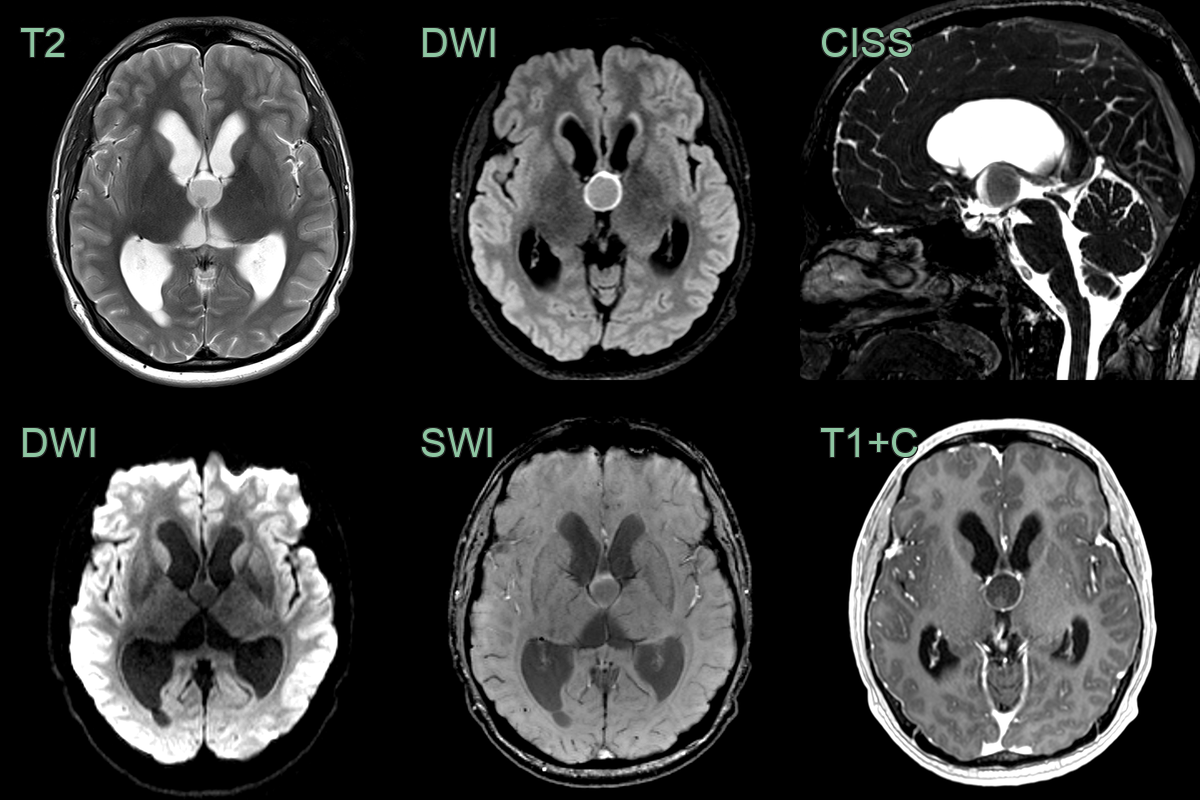

- MRI findings:

- T1-weighted: Variable signal intensity (hyperintense to CSF)

- T2-weighted: Usually hypointense to CSF

- FLAIR: Hyperintense signal

- Contrast enhancement: Typically minimal or absent

- DWI: No restricted diffusion

- 55-year-old patient presented with bladder dysfunction and unsteadiness.

- CT showed a 7 mm hyperdense lesion filling the foramen of Monro and marked enlargement of the ventricles.

- There was very little periventricular oedeam, and so the appearances suggest chronic, compensated, ventriculomeagly (rather than acute hydrocephalus).